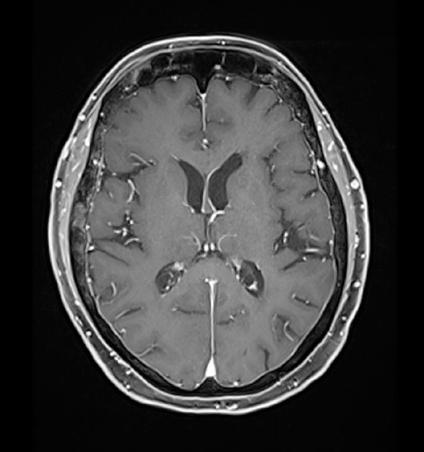

Alla RMN encefalo con mdc di approfondimento venivano evidenziate plurime lesioni ripetitive (almeno 10)

in sede sovratentoriale (diametro massimo 10x12 mm in sede temporale destra) circondate da alone di edema. Ulteriore lesione sospetta in sede sottotentoriale vermiana paramediana destra (2,5x2,5 mm circa) (figura 1a e 1b).

Figura 1a e 1b. Evoluzione della neoplasia mammaria primitiva dalla diagnosi in aprile 2023 alla risposta dopo 7 cicli di T-DXd in aprile 2024.